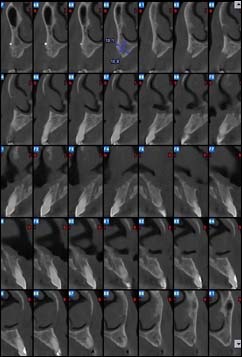

Rétroalvéolaire

Il s’agit de radios de petites tailles placées et orientées dans votre bouche et ciblant un secteur de une à trois dents. Elles permettent une vision plus précise de certains détails.

Coupe axiale

Reconstruction coronale